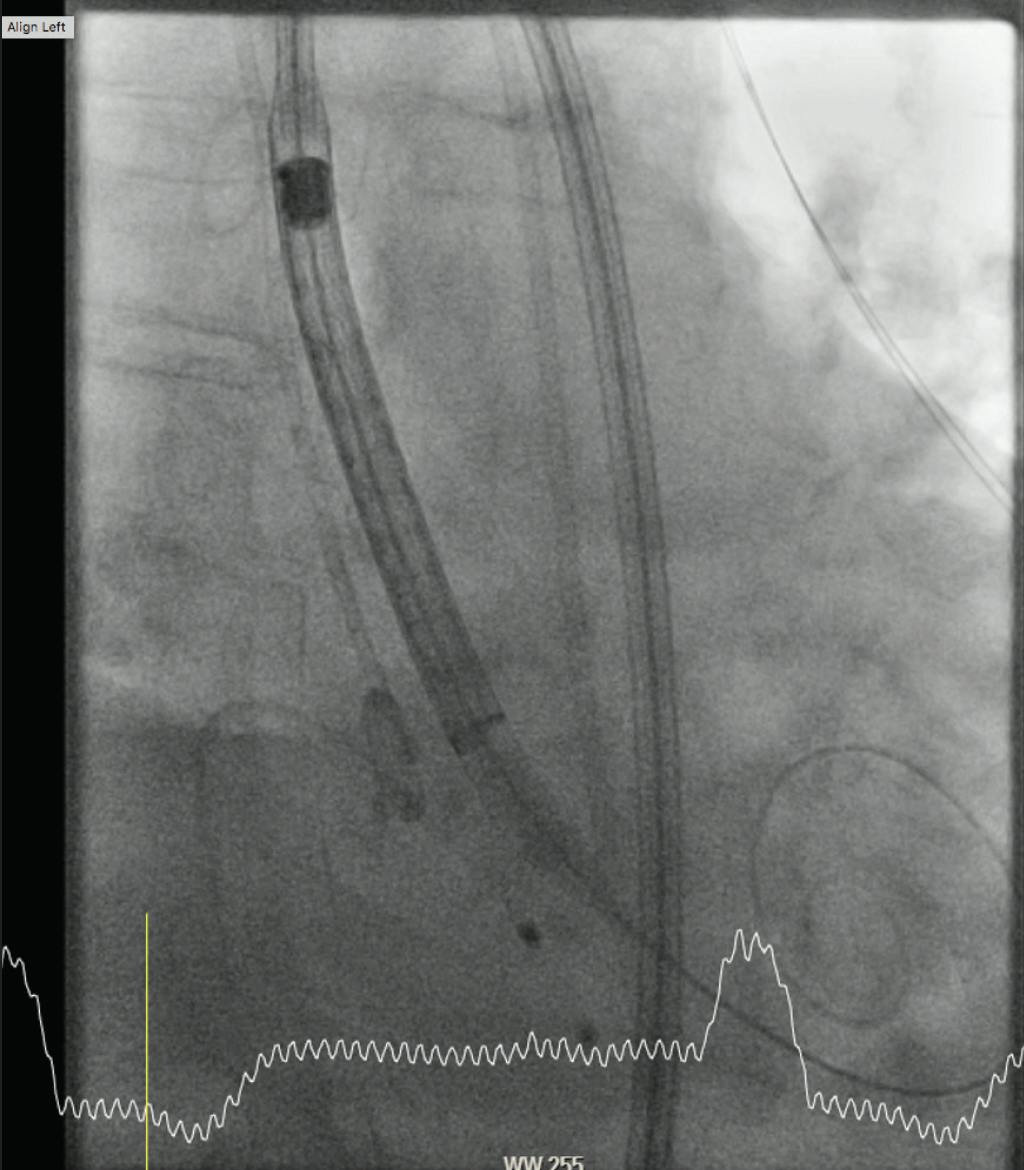

After passage of the aortic arch, the rotation of the C-arm must be adjusted according to the predefined cusp overlap view. The pigtail should be placed at the base of the noncoronary cusp. The delivery system should be advanced no further than the markerband at the level of the mid-pigtail (Figure 2). Deployment of the Evolut Pro THV should be started from this position to minimize potential interaction with the conduction system. Usually, the THV slowly dives into the annulus during controlled deployment, with small movements on the handle (stepwise quarter turns are advised).

Figure 2. Start of valve deployment with markerband at the level of mid-pigtail.